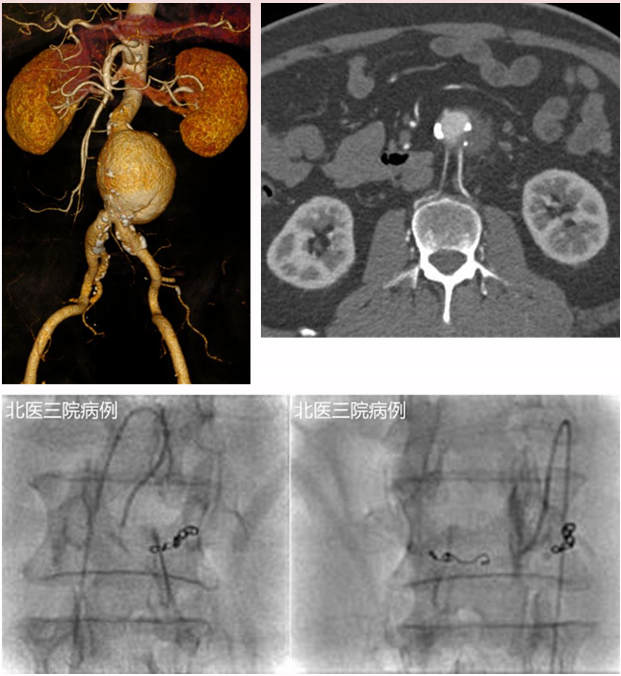

一例术前发现双侧腰动脉,因当时认为“不粗”未处理。术后 CTA 显示 II 型内漏伴瘤体增大。最终经髂内动脉入路,先以弹簧圈构建支架,再注入医用胶封闭瘤囊,成功止漏。

★ Case 1

II型内漏 预防:预栓IMA

★ Case 2

II型内漏 预防:预栓腰A